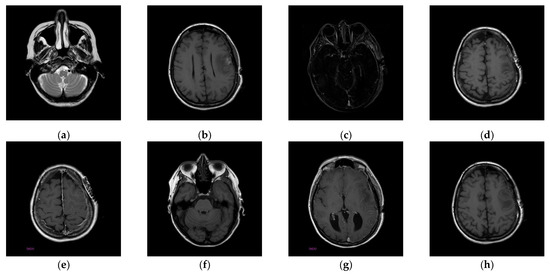

4.1. Performance of the Proposed Scheme

Once the visible watermarked image has been verified, we use the proposed inpainting scheme to remove the visible watermark and restore the original content which contains the completely restored ROI and slightly distorted RONI. The restored images are illustrated in Figure 16. We can see from Figure 16 that the restored image appears visually indistinguishable from the original image. To better illustrate the restoration quality, we magnify the restored areas for display, as shown in Figure 17. We can also observe that the enlarged restored content is visually identical to the original content.

Figure 16. The restored images. (a) Restored 10.png; (b) Restored 11.png; (c) Restored 14.png; (d) Restored 16.png; (e) Restored 19.png; (f) Restored 26.png; (g) Restored 31.png; (h) Restored 57.png.